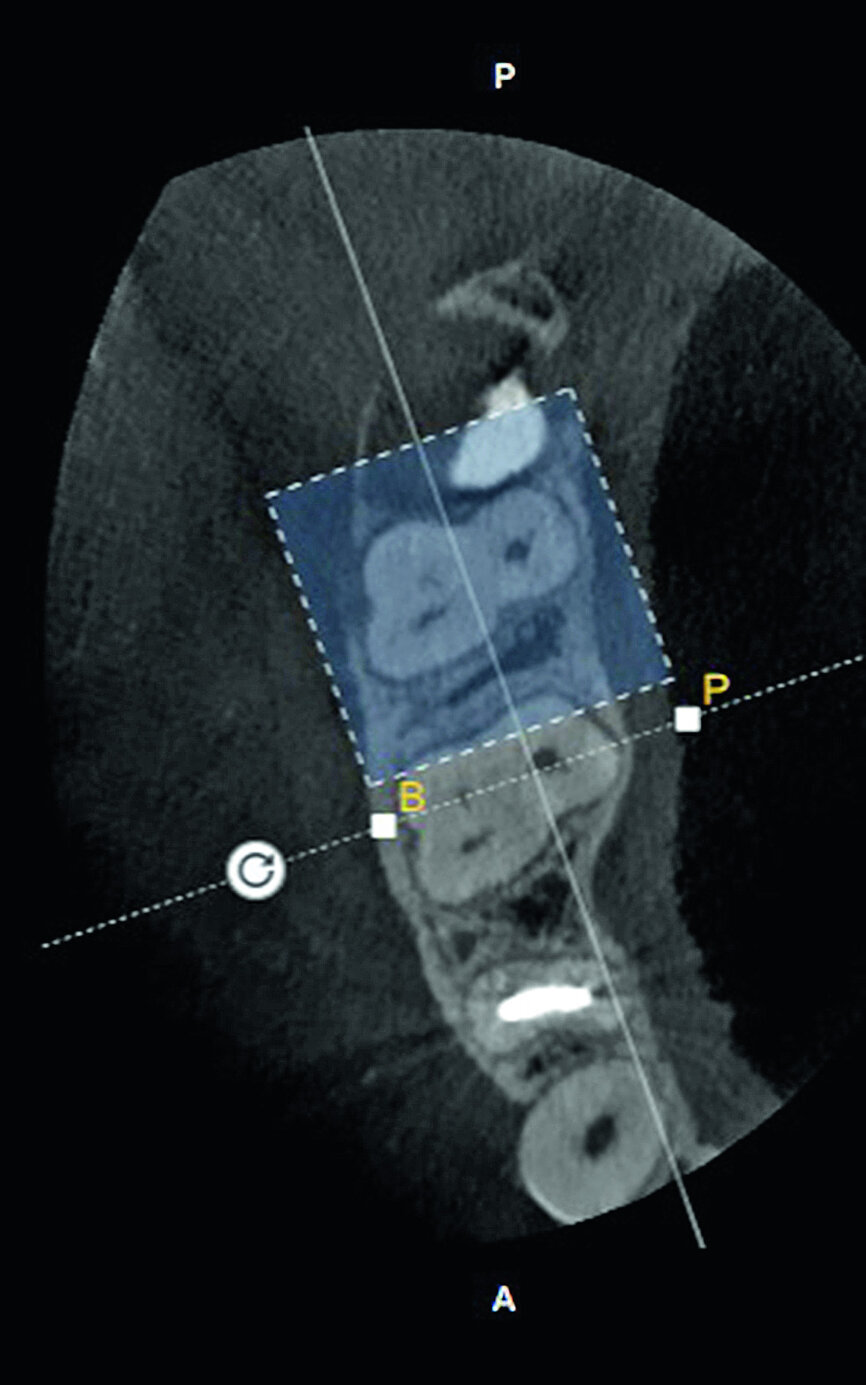

Fig. 5a: Selection of the tooth to be examined.

Fig. 5b: Selection of the tooth to be examined.

The second step, ‘3D Tooth Anatomy’, involved selecting the tooth to be examined and the entire volume was cropped to only leave the data of interest behind (Fig. 5). In the third step, ‘Canal System’, the number of root canals were identified and each root canal was then mapped separately by identifying the orifice and radiographic apical foramen of each root canal (Fig. 6).